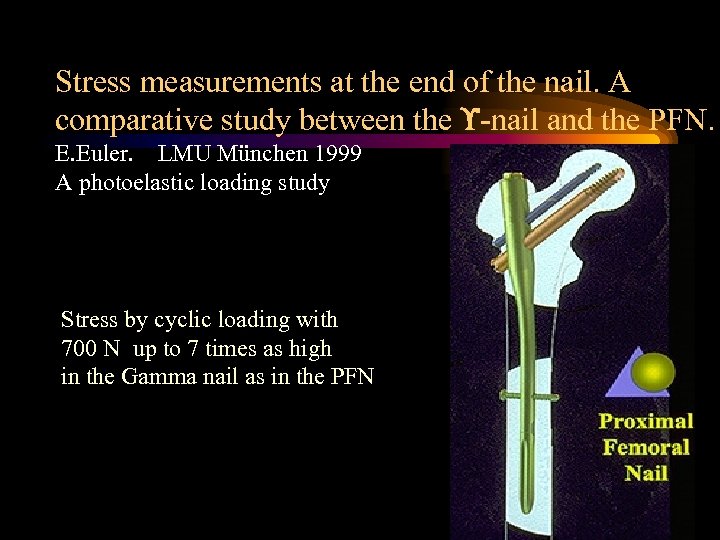

Stress measurements at the end of the nail. A comparative study between the -nail and the PFN. E. Euler. LMU München 1999 A photoelastic loading study Stress by cyclic loading with 700 N up to 7 times as high in the Gamma nail as in the PFN DHS + TSP

Stress measurements at the end of the nail. A comparative study between the -nail and the PFN. E. Euler. LMU München 1999 A photoelastic loading study Stress by cyclic loading with 700 N up to 7 times as high in the Gamma nail as in the PFN DHS + TSP